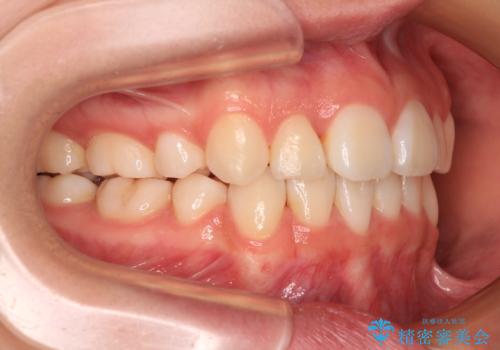

上下の骨格での左右差が小さかったことと、抜歯矯正であったことで、上下正中の位置をきれいに合わせることができました。